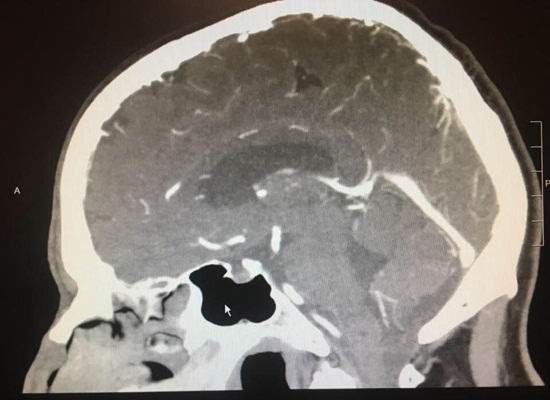

Paul Wood, ki živi v mestu Lodai, se je začel pritoževati nad glavobolom bolečine pred nekaj meseci. Ko se je Američan obrnil v bolnišnici, diagnosticirali so mu možganski tumor. Dodeljeno tvegano operacijo, pa se je dan prej nenadoma izkazalo, da je tumor preprosto izginila. Zdravniki niso verjeli svojim očem, kdaj Rentgen je pokazal, da so se bolnikovi možgani vrnili v zdravo stanje stanje.

Strokovnjaki prepoznajo, da so v redkih primerih maligni do t.i. tumor lahko sam začne regresirati popolno izginotje. Vendar za vsakršno materialistično to se ne more zgoditi v enem dnevu.

Še vedno izvajamo teste, največ uporabljamo napredna tehnologija, vendar moramo priznati, da je tumor izginil kot s čarovnijo. Včasih nekatere stvari samo ki je z znanostjo nemogoče razložiti, pravi kirurg Richard Wye, ki morali izvesti operacijo za našega junaka.